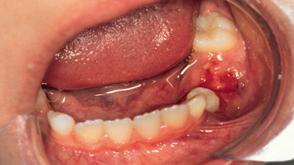

Marginal parodontitis er en plakrelateret sygdom, og plakkens sammensætning er forskellig i den supra- og den subgingivale plak. Plakken ved margo gingivae indeholder mikroorganismer, der via membranbundne komponenter og ifm. deres metabolisme